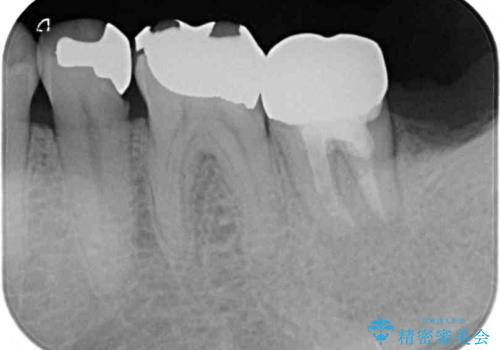

レントゲン写真より、一番奥の歯の根尖部に大きな病変(炎症により骨が溶けている状態)が認められたため、根管治療を行うこととしました。

根管治療後に痛みは一次消退しましたが、半年ほど経過しても病変は改善しておらず、歯根が破折している状態となっていました。

歯根が破折した歯は抜歯となるため、抜歯して病変の部分に骨が回復するのを待って、インプラントによる補綴治療を行うこととしました。